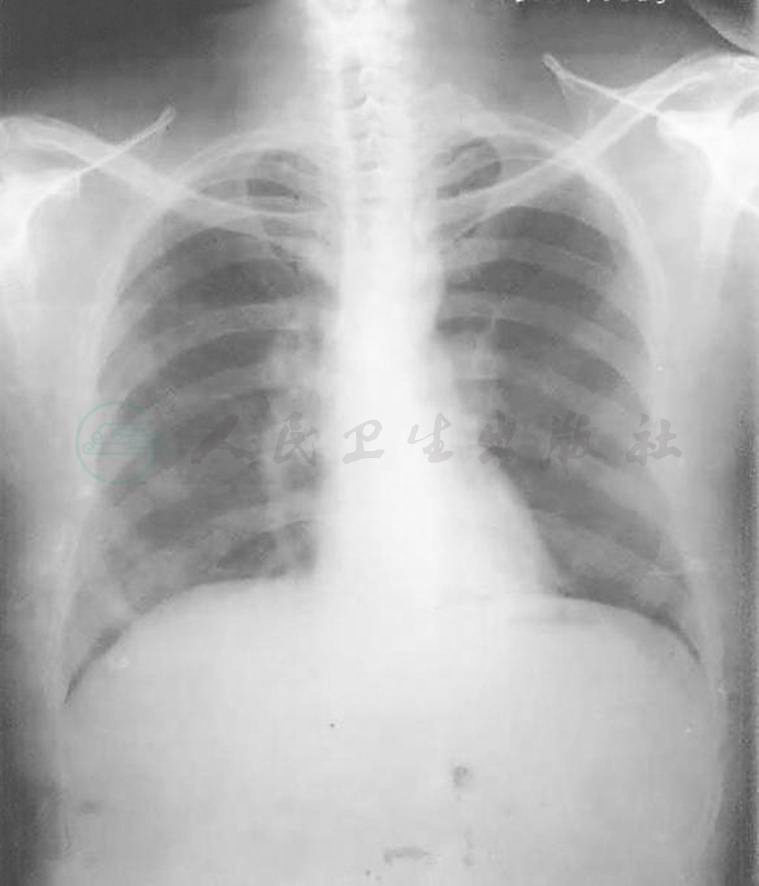

图3 12年半前胸部X线表现

胸部X线除左上肺透过度略增墙外,双肺体积大致正常